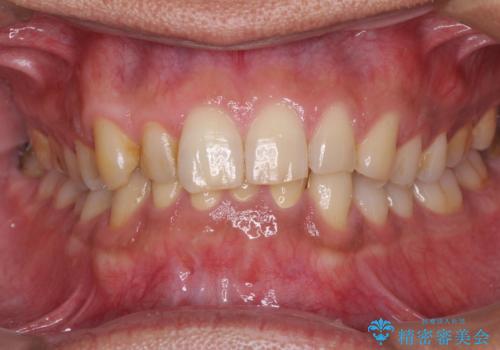

根管治療により腫れと痛みが引き、叢生の認められた歯列は補綴治療により改善され、清掃性が増しました。

歯が失活してしまうほどの咬合力であるため、就寝時にはマウスピースを装着していただくようお願いしました